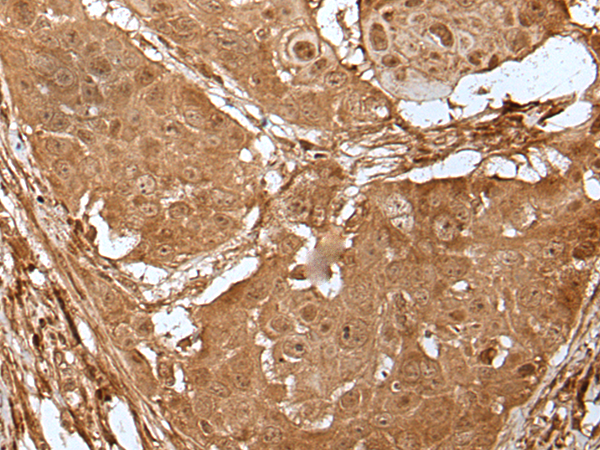

分类: 科研抗体货号: P01447别名: HDL; 11-DH; HSD11; HSD11B; HSD11L; CORTRD2; SDR26C1; 11-beta-HSD1应用: IHC反应种属: Human